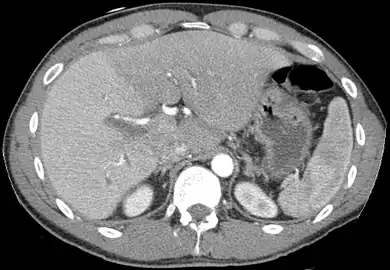

- Axial CT image showing anomalous hepatic veins coursing on the liver's subcapsular anterior surface[70]

- Maximum intensity projection (MIP) CT image as viewed anteriorly showing the anomalous hepatic veins coursing on the anterior surface of the liver

- Lateral MIP view in the same patient as previous image

- A CT scan in which the liver and portal vein are shown